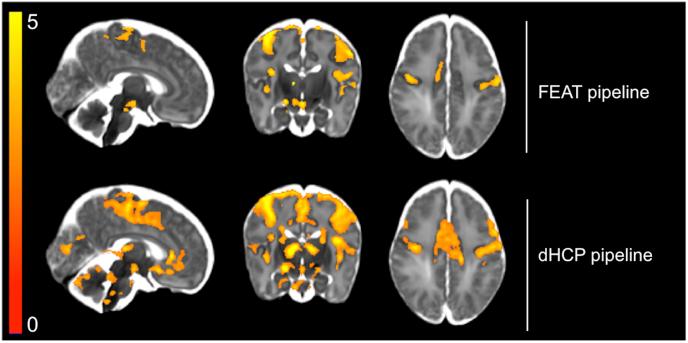

The infant brain is unlike the adult brain, with considerable differences in morphological, neurodynamic, and haemodynamic features. As the majority of current MRI analysis tools were designed for use in adults, a primary objective of the Developing Human Connectome Project (dHCP) is to develop optimised methodological pipelines for the analysis of neonatal structural, resting state, and diffusion MRI data. Here, in an independent neonatal dataset we have extended and optimised the dHCP fMRI preprocessing pipeline for the analysis of stimulus-response fMRI data. We describe and validate this extended dHCP fMRI preprocessing pipeline to analyse changes in brain activity evoked following an acute noxious stimulus applied to the infant's foot. We compare the results obtained from this extended dHCP pipeline to results obtained from a typical FSL FEAT-based analysis pipeline, evaluating the pipelines' outputs using a wide range of tests. We demonstrate that a substantial increase in spatial specificity and sensitivity to signal can be attained with a bespoke neonatal preprocessing pipeline through optimised motion and distortion correction, ICA-based denoising, and haemodynamic modelling. The improved sensitivity and specificity, made possible with this extended dHCP pipeline, will be paramount in making further progress in our understanding of the development of sensory processing in the infant brain.